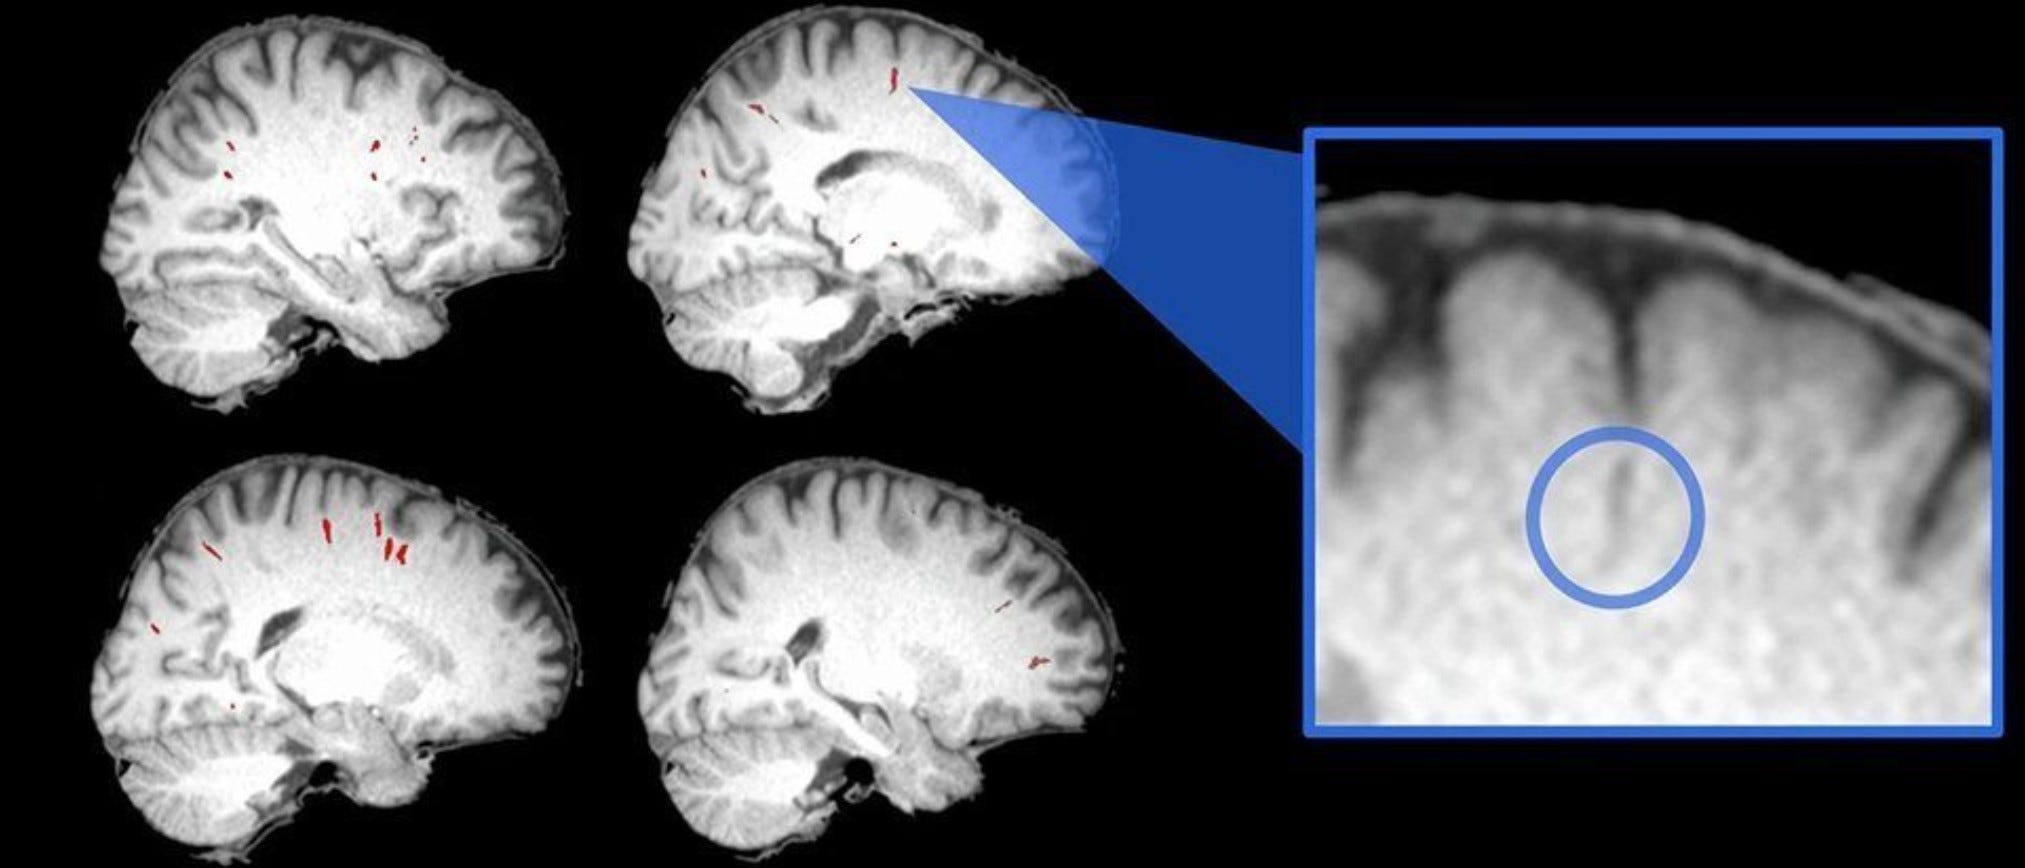

Astronauts experience distinct brain changes for months after they return to Earth…